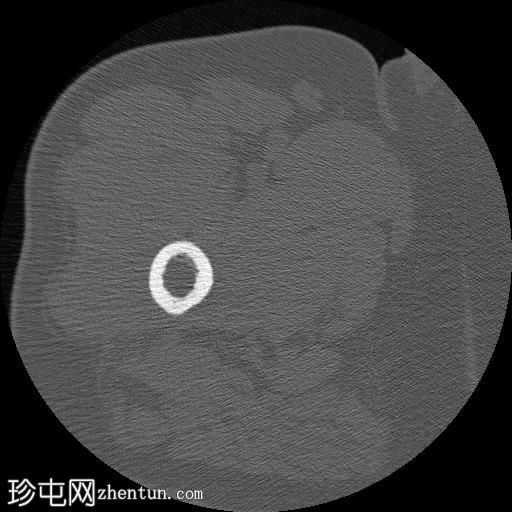

轴位骨窗

右股骨近端干骺端,股骨大转子下方可见一边界清晰的溶骨性病变。

未见皮质破坏及骨膜反应。